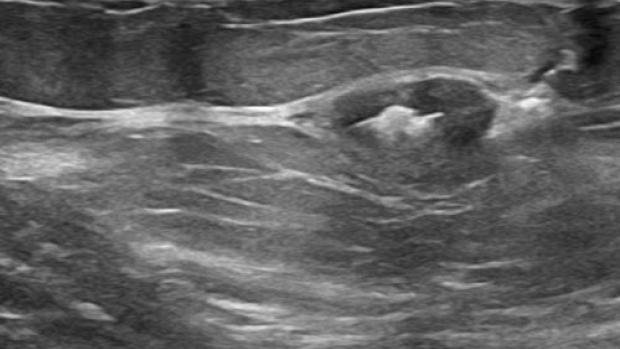

Tumark Professional Q and U markers are sandblasted nitinol, designed to provide outstanding visibility in ultrasound, and excellent visibility under mammography at deployment. In 85% of marker placements, physicians stated the ultrasound visibility was good to excellent upon deployment.2

In the initial data collection study: 91% of markers placed under ultrasound did not migrate, as measured on the post-procedure mammogram.1 In 9 out of 10 cases the marker deployed accurately in ultrasound to the intended area.1